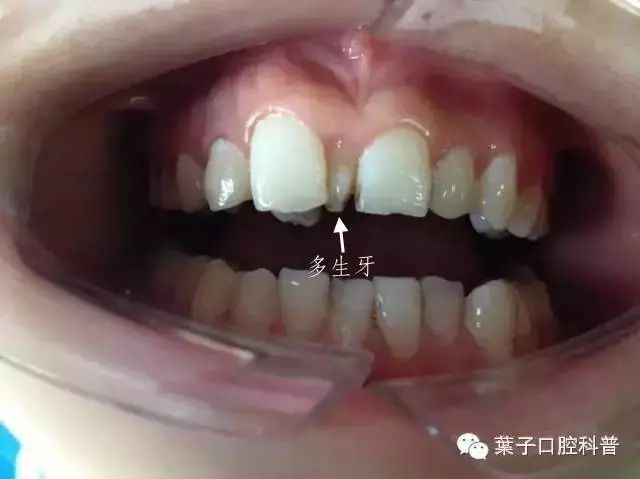

多生牙 —— 顾名思义,就是多余长出来的牙齿,最常见的是上颌“正中多生牙”,也就是长在门牙之间的牙齿。

一般来说,单侧或对称都有可能生长,有的已经萌出,有的会埋伏阻生,有的甚至会倒着长。多生牙一般是小锥形,牙根较短。

门牙缝大需留意,孩子可能有多生牙

从小姑娘的照片中可以看到,她的侧切牙已经长了,但门牙之间缝隙还是很大。拍X线片检查后,果然发现有多生牙,而且是两颗。

案例中小姑娘的多生牙是属于埋伏生长。还有一种情况是,“长出来”了的多生牙。

这是一位刚开始换牙的小朋友,新换出来的牙齿特别小,而且是锥形的。家长还以为是门牙形状畸形,带着来医院检查,才发现原来这是多生牙。